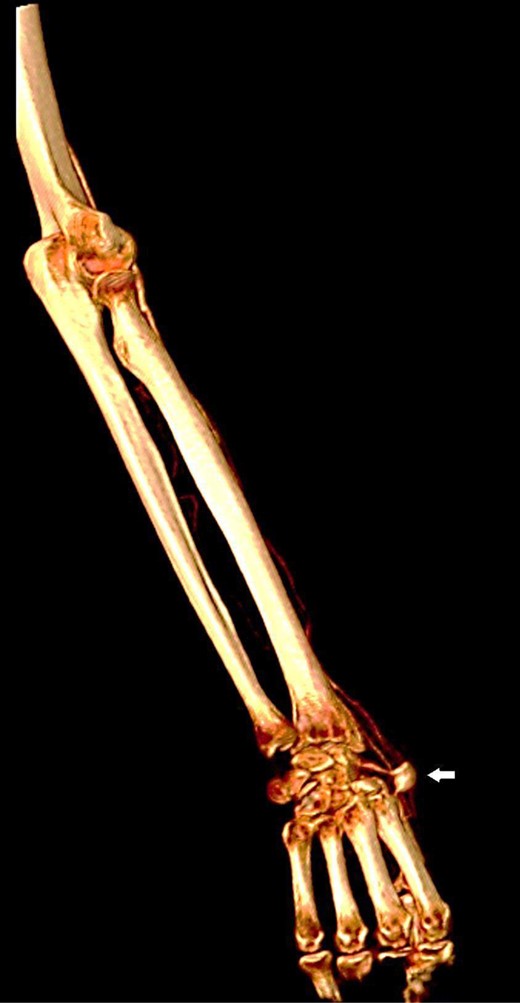

Upon physical examination, a mass of 2-by-3 cm found at the anatomical snuffbox area of the right hand, with no visible scars (Fig. 1). The mass was pulsatile, and no bruit was detected. The examination of the other arteries was negative. Later, CT angiography detected a local dilation at the distal part of the right radial artery (Figs 2 and 3). Complete body scan showed another aneurysm at the right common iliac artery measured 3-by-2.8 cm for which the patient was referred to a higher centre for possible endo-vascular intervention as it is not available in our hospital.

Reconstructed three-dimensional image shows radial artery saccular aneurysm (arrow).